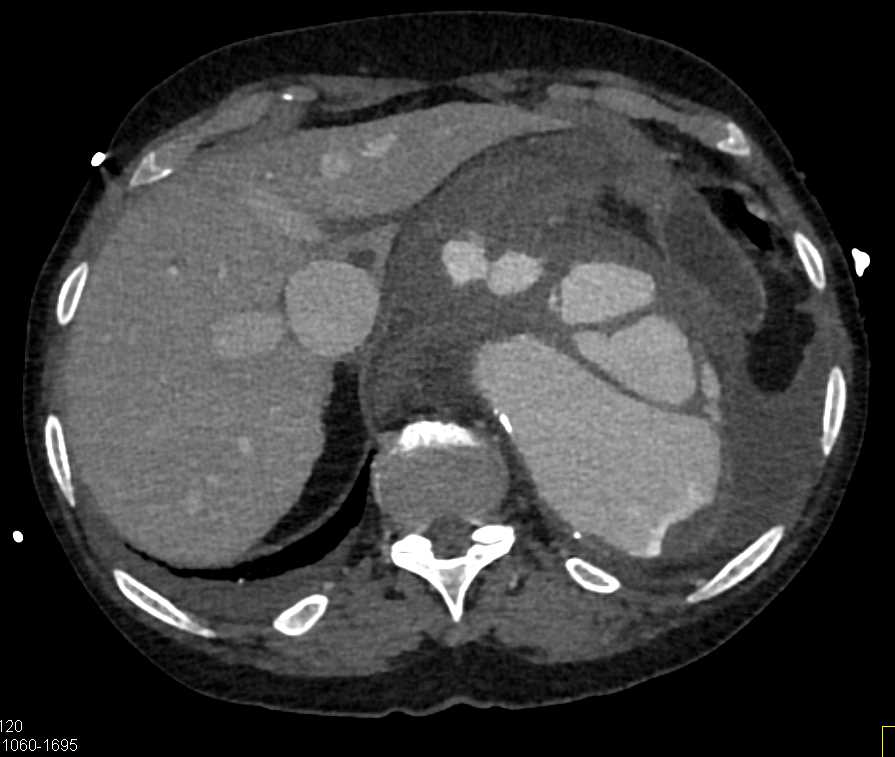

Aortic Valve Replacement (AVR) Repair and Repair of the Ascending Aorta